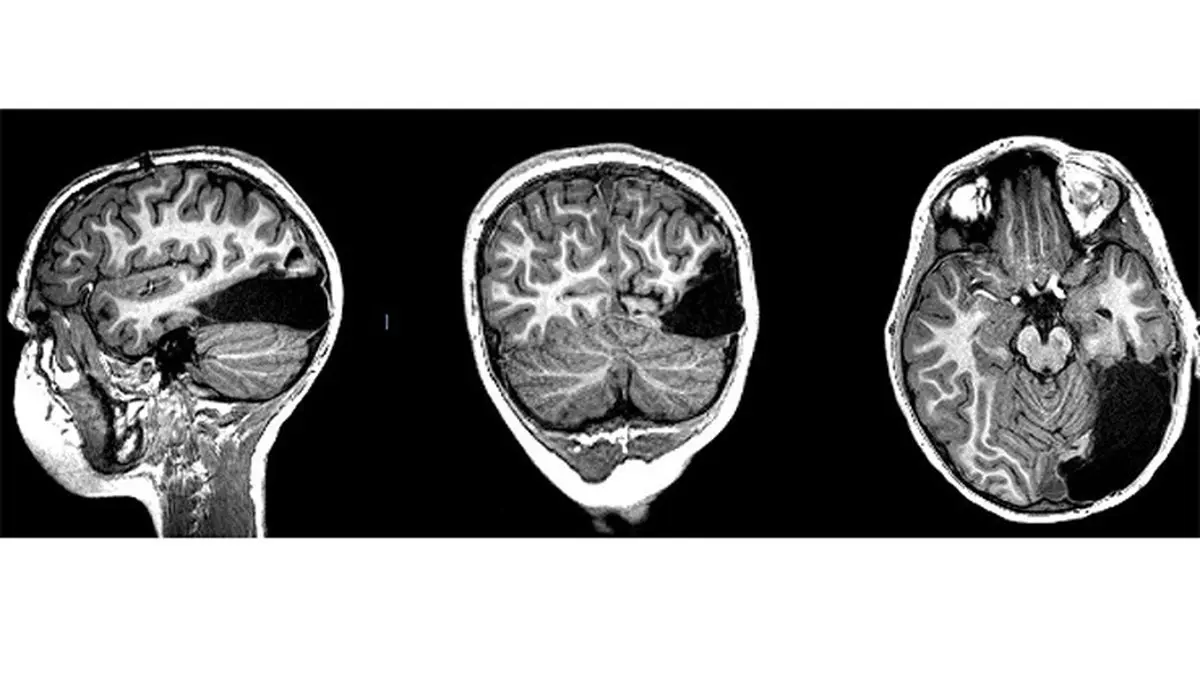

براساس گزارش «ساینس آلرت»، یک پسر ۷ ساله تحت عمل جراحی «لوببرداری (جراحی مغز)» قرار گرفت و یک ششم نیمکره راست مغزش را از دست داد.

پزشکان لوب پسسری او را که برای پردازش بینایی مهم است برداشتند.

آنچه که پزشکان پس از عمل جراحی وی دریافتند بسیار شگفتانگیز بود. اگرچه او با از دست دادن بخشی از مغزش قادر به دیدن سمت چپش نیست، اما به طور باورنکردنی نیمکره سمت چپ او وظایف دیداری نیمکره راست را جبران میکند.